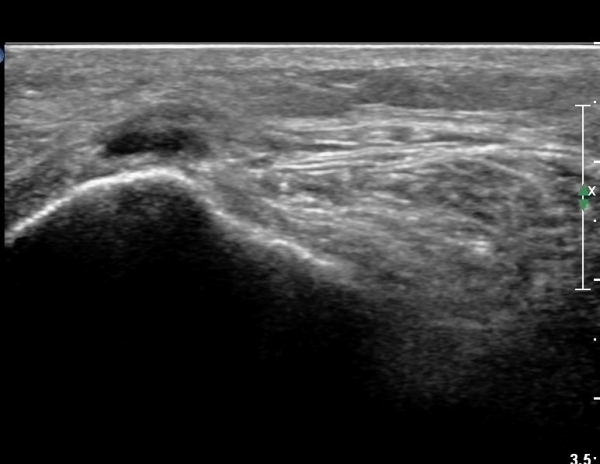

ŽÃËÀÚ¸¦ Á» ´õ ¸»´ÜÀ¸·Î À̵¿ÇÏ´Ï ºñ°ñ °æºÎ Ç¥Ãþ¿¡¼­ ºñ°ñ½Å°æÀÌ °üÂûµÇ°í(»çÁø 6, 7),

ºñ°ñ±Ù ½ÉºÎÀÇ ºñ°ñ °æºÎ¿¡¼­ °üÂûµÈ´Ù(»çÁø 8).